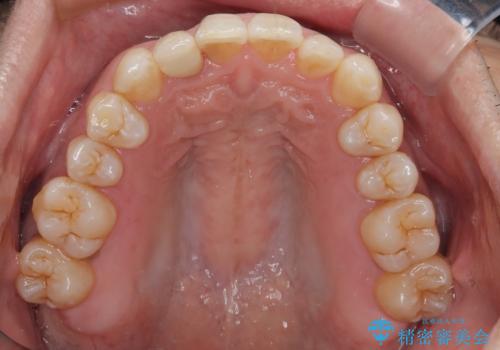

担当医としてはもう少し前歯のデコボコを改善したいところでしたが、患者様としては十分に満足いく歯列であり、マウスピース矯正に飽きてしまったとのことで、治療終了となりました。